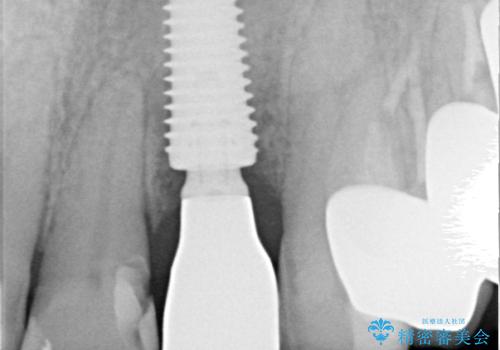

診察をしたところ、歯根に縦破折が認められ、抜歯が必要と判断されました。

抜歯、インプラント埋入、仮歯の装着が同時に可能な1DAYインプラントが適用可能と判断されたため、インプラントによる補綴治療を行うこととしました。